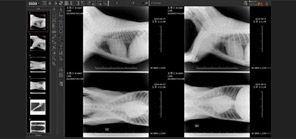

EMR Embedded PACS

- The first embedment in the electronic chart of veterinary clinics in the world

- Composition of one perfect system by combining EMR with PACS

- Innovative integral system getting out of the simple connection

from the existing PACS and electronic chart - Possible to confirm the previous PACS image in the IntoVetGE

- Easy image inquiry through the Work List in the IntoVetGE Today